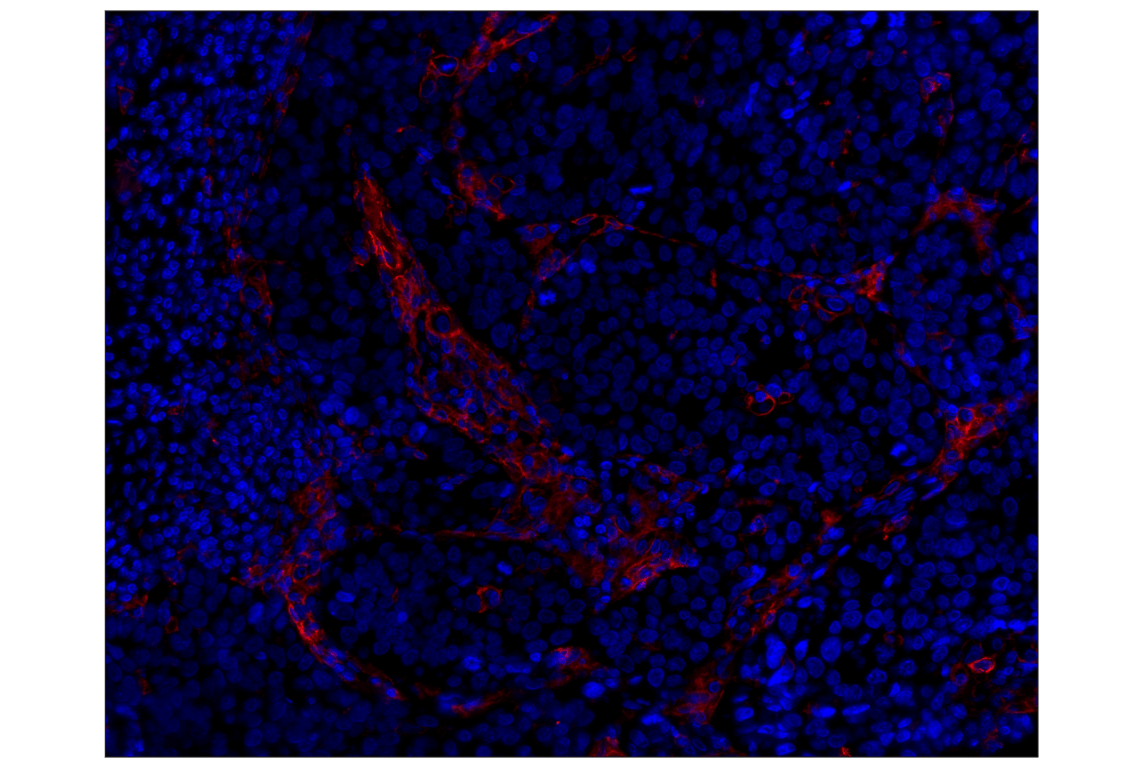

CD14 (D7A2T) Rabbit Monoclonal Antibody (Alexa Fluor® 555 Conjugate) #95166

This Cell Signaling Technology® antibody is conjugated to Alexa Fluor® 555 fluorescent dye under optimal conditions. This antibody conjugate is expected to exhibit the same species cross-reactivity as the unconjugated CD14 (D7A2T) Rabbit mAb #75181.

Immunohistochemistry (Paraffin) 1:50

CD14 (D7A2T) Rabbit Monoclonal Antibody (Alexa Fluor® 555 Conjugate) recognizes endogenous levels of total CD14 protein.

Monoclonal antibody is produced by immunizing animals with a synthetic peptide corresponding to residues surrounding Pro319 of human CD14 protein.